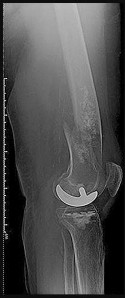

A 70-year-old female undergoes a primary posterior-stabilized total knee arthroplasty. Intraoperatively, the surgeon realizes that the knee is well-balanced in extension but unacceptably tight in flexion. Which of the following technical errors most frequently causes an isolated tight flexion gap?

Explanation

The flexion gap in TKA is dictated primarily by the size of the posterior femoral condyles and the AP dimension of the femoral component. Oversizing the femoral component in the AP dimension (and specifically adding posterior offset) stuffs the posterior joint space, leading to a tight flexion gap. Excessive distal femoral resection affects the extension gap (making it loose). Increasing the posterior tibial slope would actually increase (loosen) the flexion gap.